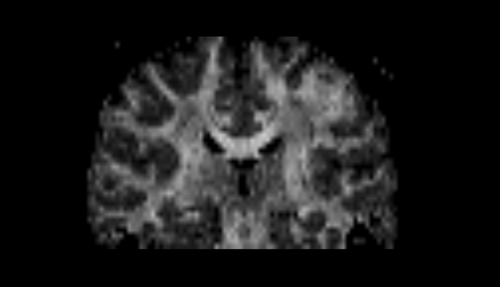

generate a brain mask,

create a DTI (Diffusion Tensor Image) tensor with standard measures like fractional anisotropy (FA), mode and trace,